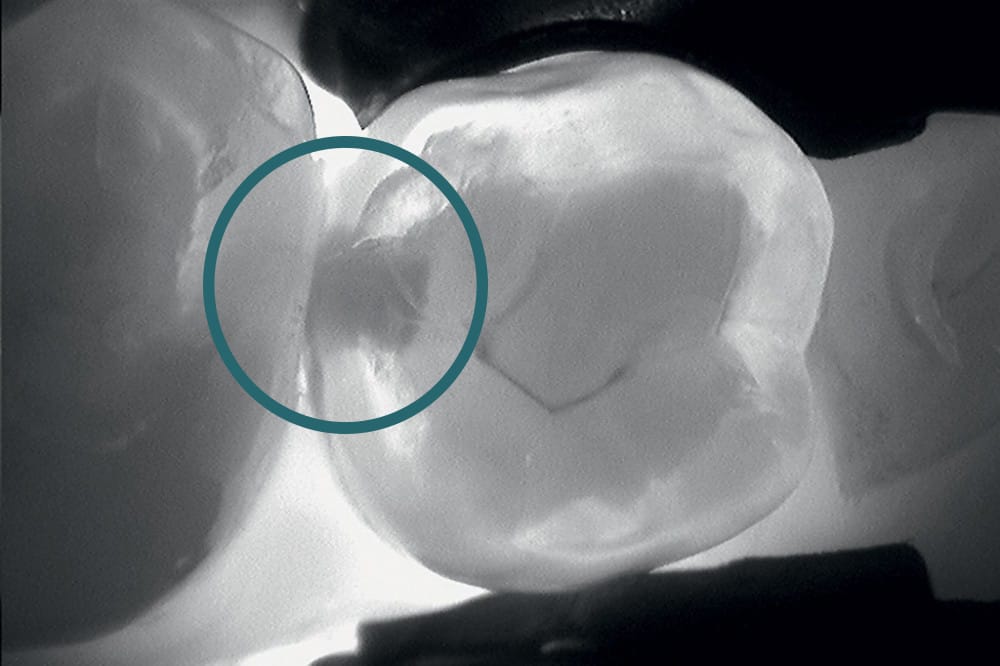

La DIAGNOCam KAVO Vision Full HD est un outil de diagnostic dentaire non invasif et sans rayons X.

Il permet de détecter les caries occlusales et proximales ainsi que les fissûres, de manière totalement indolore.

Cette caméra utilise la transillumination* (par fibre optique) ainsi que la fluorescence pour un diagnostic complet.

Avantages : méthode rapide, sans douleur et répétable car inoffensive. Ce qui offre une alternative sécurisée, notamment pour les enfants et les femmes enceintes.

*La transillumination consiste à projeter une lumière intense (infrarouge) à travers les tissus pour visualiser par transparence les lésions.

Celles-ci apparaissent en sombre car la structure dentaire saine, laisse passer la lumière contrairement aux tissus carieux.